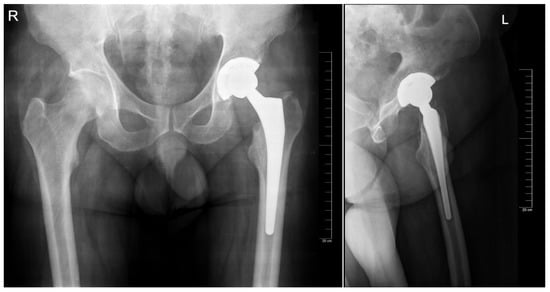

The preoperative planning was performed manually in several phases. Starting with the anteroposterior view, the X-ray magnification is determined. Next, the landmarks are identified: the center of the femoral head, teardrop, anatomical axis of the non-target femur, and the ilioischial and transacetabular teardrop lines (Figure 1). The acetabular component size that fits the contour of the acetabulum was selected. The medial border is defined as the teardrop, and the cup is placed at 45 degrees of abduction. Afterward, the femoral component size that fits most precisely the contour of the canal is chosen, keeping in mind that it should be in contact with the lateral and medial cortex and must be in line with the anatomical axis of the femur. The upper part of the stem component must be located in the piriform fossa. The leg length discrepancy (LLD) is determined by the perpendicular distance from the middle of the lesser trochanter to the horizontal line drawn through the base of both teardrops, and the femoral medial offset (FMO) is calculated as the distance from the center of the femoral head perpendicular to the anatomical axis of the femur. The planning is performed on the lateral view using a similar approach (Figure 2). The acetabular template cup of appropriate size is placed with approximately 45 degrees of abduction. The medial border of the acetabular cup is positioned next to the ilioischial line and in close contact with the teardrop. The anatomical axis of the femur is marked, and the suitable femoral stem is chosen and positioned to fill the medullary canal. Postoperative radiographs are routinely performed to confirm proper positioning (Figure 3).

Figure 2. Templating of the femoral and acetabular components on the anteroposterior and lateral view, respectively. Note that there is one size difference in the estimation for each component between plans on the two views.